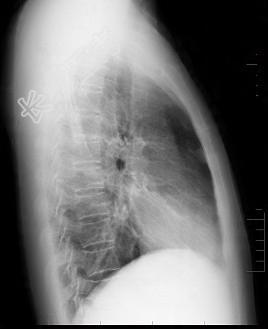

- 单项选择题男性患者,38岁, 突感胸部不适,X线检查如图, 最可能的诊断是 ( )

A、肺部炎症

B、胸腔积液

C、肺结核

D、正常心、肺、膈

E、气胸